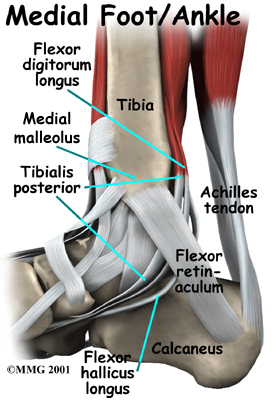

Anatomy

Where is the posterior tibial tendon, and what does it do?

The posterior tibial tendon runs behind the inside bump on the ankle (the medial malleolus), across the instep, and into the bottom of the foot. The tendon is important in supporting the arch of the foot and helps turn the foot inward during walking.

Problems with the posterior tibial tendon seem to occur in stages. Initially, irritation of the outer covering of the tendon, called the paratenon, causes paratendonitis. This means that there is inflammation between the lining of the tendon and the tendon itself where it runs through the tunnel behind the medial malleolus. This tendonitis can start a process of wear and tear on the tendon fibers.

Muscle testing helps identify any areas of weakness or muscle impairment and imbalance. This will be done in both the weight bearing and non-weight bearing positions. As briefly mentioned above, an important test that can help identify insufficiency of the posterior tibial tendon is the single heel raise. You therapist will ask you to stand on one foot and rise up on your toes. You should be able to lift your heel off the ground easily while keeping the heel bone (calcaneus) centered and slightly turned inward (inverted) and your knees straight. If you cannot, your posterior tibialis muscle and tendon may be ruptured.